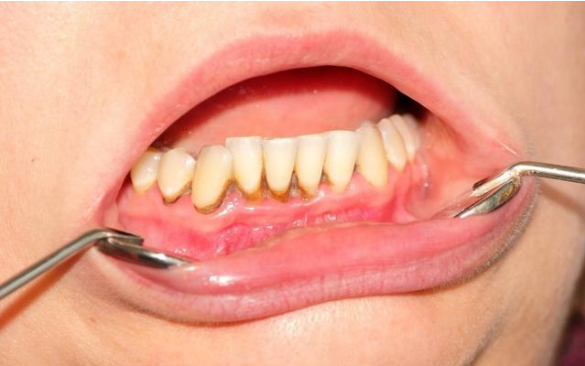

1.牙周病

刷牙方法不正确、没做好清洁,容易造成牙龈发炎。牙龈长期发炎会导致周围的牙槽骨吸收,牙龈炎发展成牙周炎,牙龈就会慢慢萎缩,这样就产生了较大的牙缝。牙周炎还会逐渐导致牙齿松动移位,导致塞牙进一步加重!